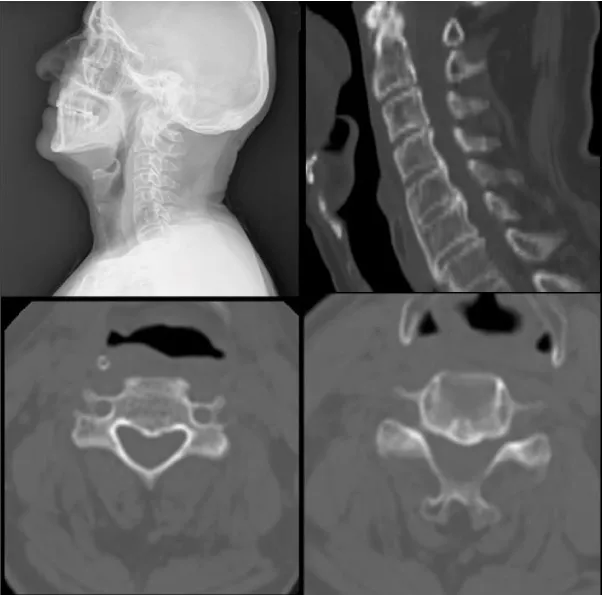

A 65- year old male patient with history of diabetes mellitus was admitted to our outpatient clinic with neck pain, dysphagia and sleep apnea for over 5 months. Previously evaluated by the otolaryngology department a esophagography a slight compression of the upper cervical esophagus segment was observed. He stated that he lost 6kg in 6months due to the dysphagia. On his cervical CT scan revealed broad ossification of the anterior longitudinal ligament from C2 to T1 with anteriorly beaking osteophytes surrounding the vertebral bodies causing compression of the trachea and esophagus on C2 and C3 (Figure 1). Magnetic Resonance Imaging (MRI) showed that there were no disc pathologies; vertebral heights and spinal alimentation were normal. The spinal canal and spinal cord were intact. (Figure 2). With the diagnosis of DISH, the patient underwent surgery. With an anterolateral approach the ossified pathological segment was removed with a high-speed drill and no compression of the surrounding soft tissue fractures were confirmed. The patient’s symptoms revealed immediately after the surgery and on the postoperative control CT scan, total clearance of the ossified structures were observed (Figure 3).